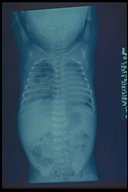

Chest X-ray finding in a case of cystic adenomatoid right lung